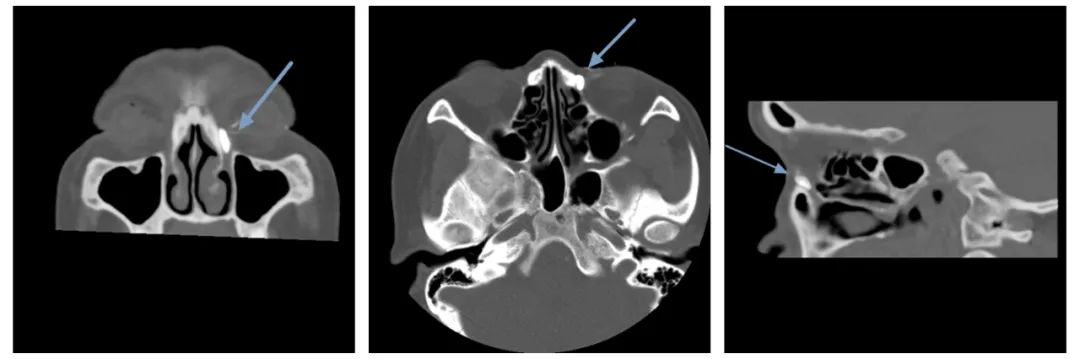

泪囊造影CT

泪囊造影CT具有全面无创评估泪道系统及邻近组织结构的优点,图像分辨率高,对泪道全程对比剂显影清晰,有利于判断和评估完全阻塞和部分阻塞及阻塞部位,已成为术前评估、疗效和预后预测以及术后复查的常用方法